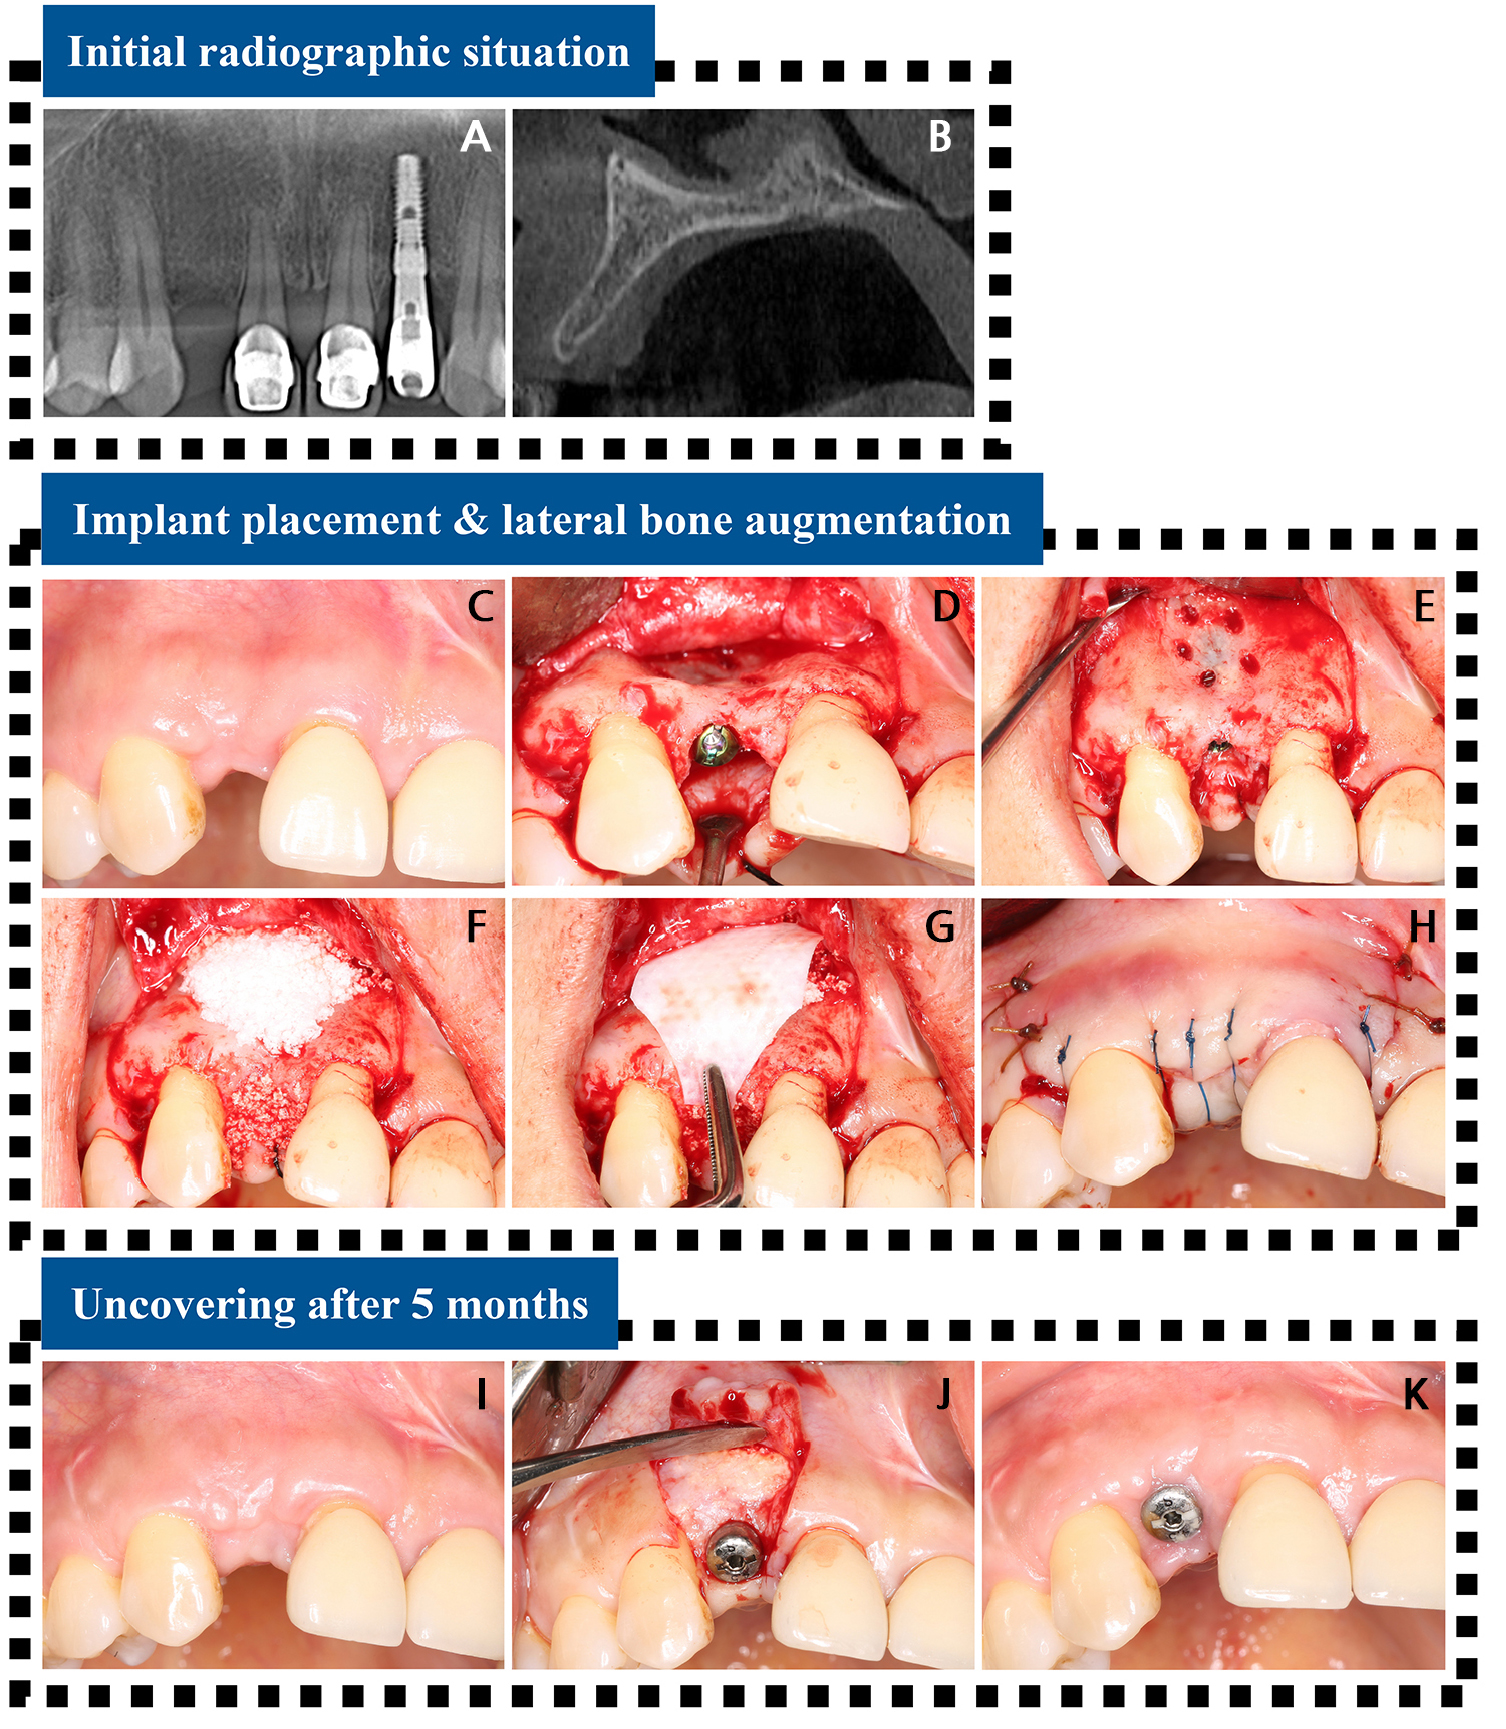

- Late Onset Lateral Peri-implantitis at Maxillary Anterior Implant Site: A Case Report

- Won-Bae Park, Borvornwut Buranawat, Seung-Il Shin, Hyun-Chang Lim

- Peri-implant inflammation may originate at the lateral surface of the implant, a condition known as lateral peri-implantitis; however, the condition remains underrecognized …

- Peri-implant inflammation may originate at the lateral surface of the implant, a condition known as lateral peri-implantitis; however, the condition remains underrecognized among clinicians. A 42-year-old non-smoking female patient underwent implant placement and lateral ridge augmentation in the anterior maxillary area (#12). The healing process was uneventful, and the implant functioned successfully without any adverse events. However, after 7 years, the patient reported tenderness at the implant site. The cone-beam computed tomography (CBCT) scan revealed a labial depression in the augmented tissue and loss of radiopacity. During surgical re-entry, a large bone defect encompassing two-thirds of the implant was identified. The exposed implant surface was decontaminated using titanium curettes, a titanium brush, and a tetracycline-hydrochloride solution (for 5 minutes). Bone grafting was performed on the defective area, followed by connective tissue grafting. The implant site healed uneventfully, and successful integration of the reaugmented bone was confirmed by CBCT scan 1 year after re-entry. No specific complications were noted. Although lateral peri-implantitis is rare, it can compromise the long-term stability of implants, underscoring the importance of understanding this condition. - COLLAPSE